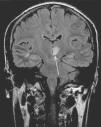

Meningitis tuberculosa con infartos cerebrales

Cerebral infarctions in tuberculous meningitis